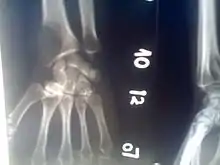

Osteolytic lesion at the bottom of the radius, diagnosed by a darker section that indicates a loss of bone density.

An osteolytic lesion (from the Greek words for "bone" (ὀστέον), and "to unbind" (λύειν)) is a softened section of a patient's bone formed as a symptom of specific diseases, including breast cancer and multiple myeloma. This softened area appears as a hole on X-ray scans due to decreased bone density, although many other diseases are associated with this symptom.[1] Osteolytic lesions can cause pain, increased risk of bone fracture, and spinal cord compression.[2] These lesions can be treated using biophosphonates or radiation, though new solutions are being tested in clinical trials.

The most common cancers that metastasize to form osteolytic lesions are thyroid, lung, kidney, gastrointestinal, malignant melanoma and breast, though any cancer can cause bone lesions. Lesions are most often found in larger bones, such as the skull, pelvis, radius, and femur.[3][4]